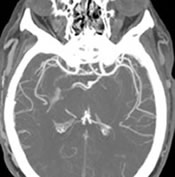

• Arteriograms – A scan that uses X-rays, contrast, or dye to see inside the arteries.

• Angiograms – A scan that uses X-rays, computed tomography angiography (CTA) or magnetic resonance angiography (MRA) to show the blood flow through the arteries or veins.